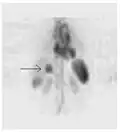

Iodine-123 whole body scan for thyroid cancer evaluation. The study above was performed after the total thyroidectomy and TSH stimulation with thyroid hormone medication withdrawal. The study shows a small residual thyroid tissue in the neck and a mediastinum lesion, consistent with the thyroid cancer metastatic disease. The observable uptakes in the stomach and bladder are normal physiologic findings.